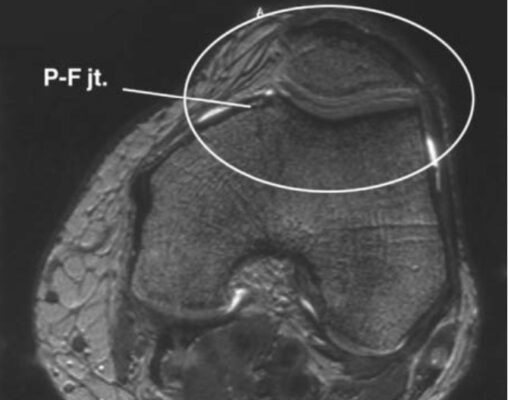

Khớp bánh chè đùi (patellofemoral joint)

Khớp giữa xương bánh chè với rãnh ròng rọc của xương đùi.

Xương bánh chè là một xương vừng hình tam giác bị bao quanh bởi các gân của cơ tứ đầu đùi. Vai trò chính của xương bánh chè là gia tăng thuận lợi cơ học của cơ tứ đầu đùi.

Mặt sau của xương bánh chè được bao phủ bởi một lớp sụn rất dày. Một gờ xương dọc chia mặt sau xương bánh chè thành các mặt trong và ngoài, và mỗi mặt có thể được chia thành mặt khớp nhỏ trên, giữa và dưới. Có một mặt thứ bảy, được gọi là mặt lẻ (odd facet), ở mặt trong cùng của xương bánh chè. Trong động tác gấp duỗi bình thường, thường có năm mặt khớp nhỏ này tiếp xúc với xương đùi.

Xương bánh chè kết nối với lồi củ chày qua gân bánh chè rất chắc. Nó được nối với xương đùi và xương chày bởi các dây chằng bánh chè-đùi và bánh chè-chày mà thật ra là sự dày lên của mạc cơ duỗi bao quanh khớp..

LIÊN HỆ X QUANG KHỚP GỐI

Ghi chú viết tắt:

- FT = Femoral trochlear groove; rãnh ròng rọc xương đùi